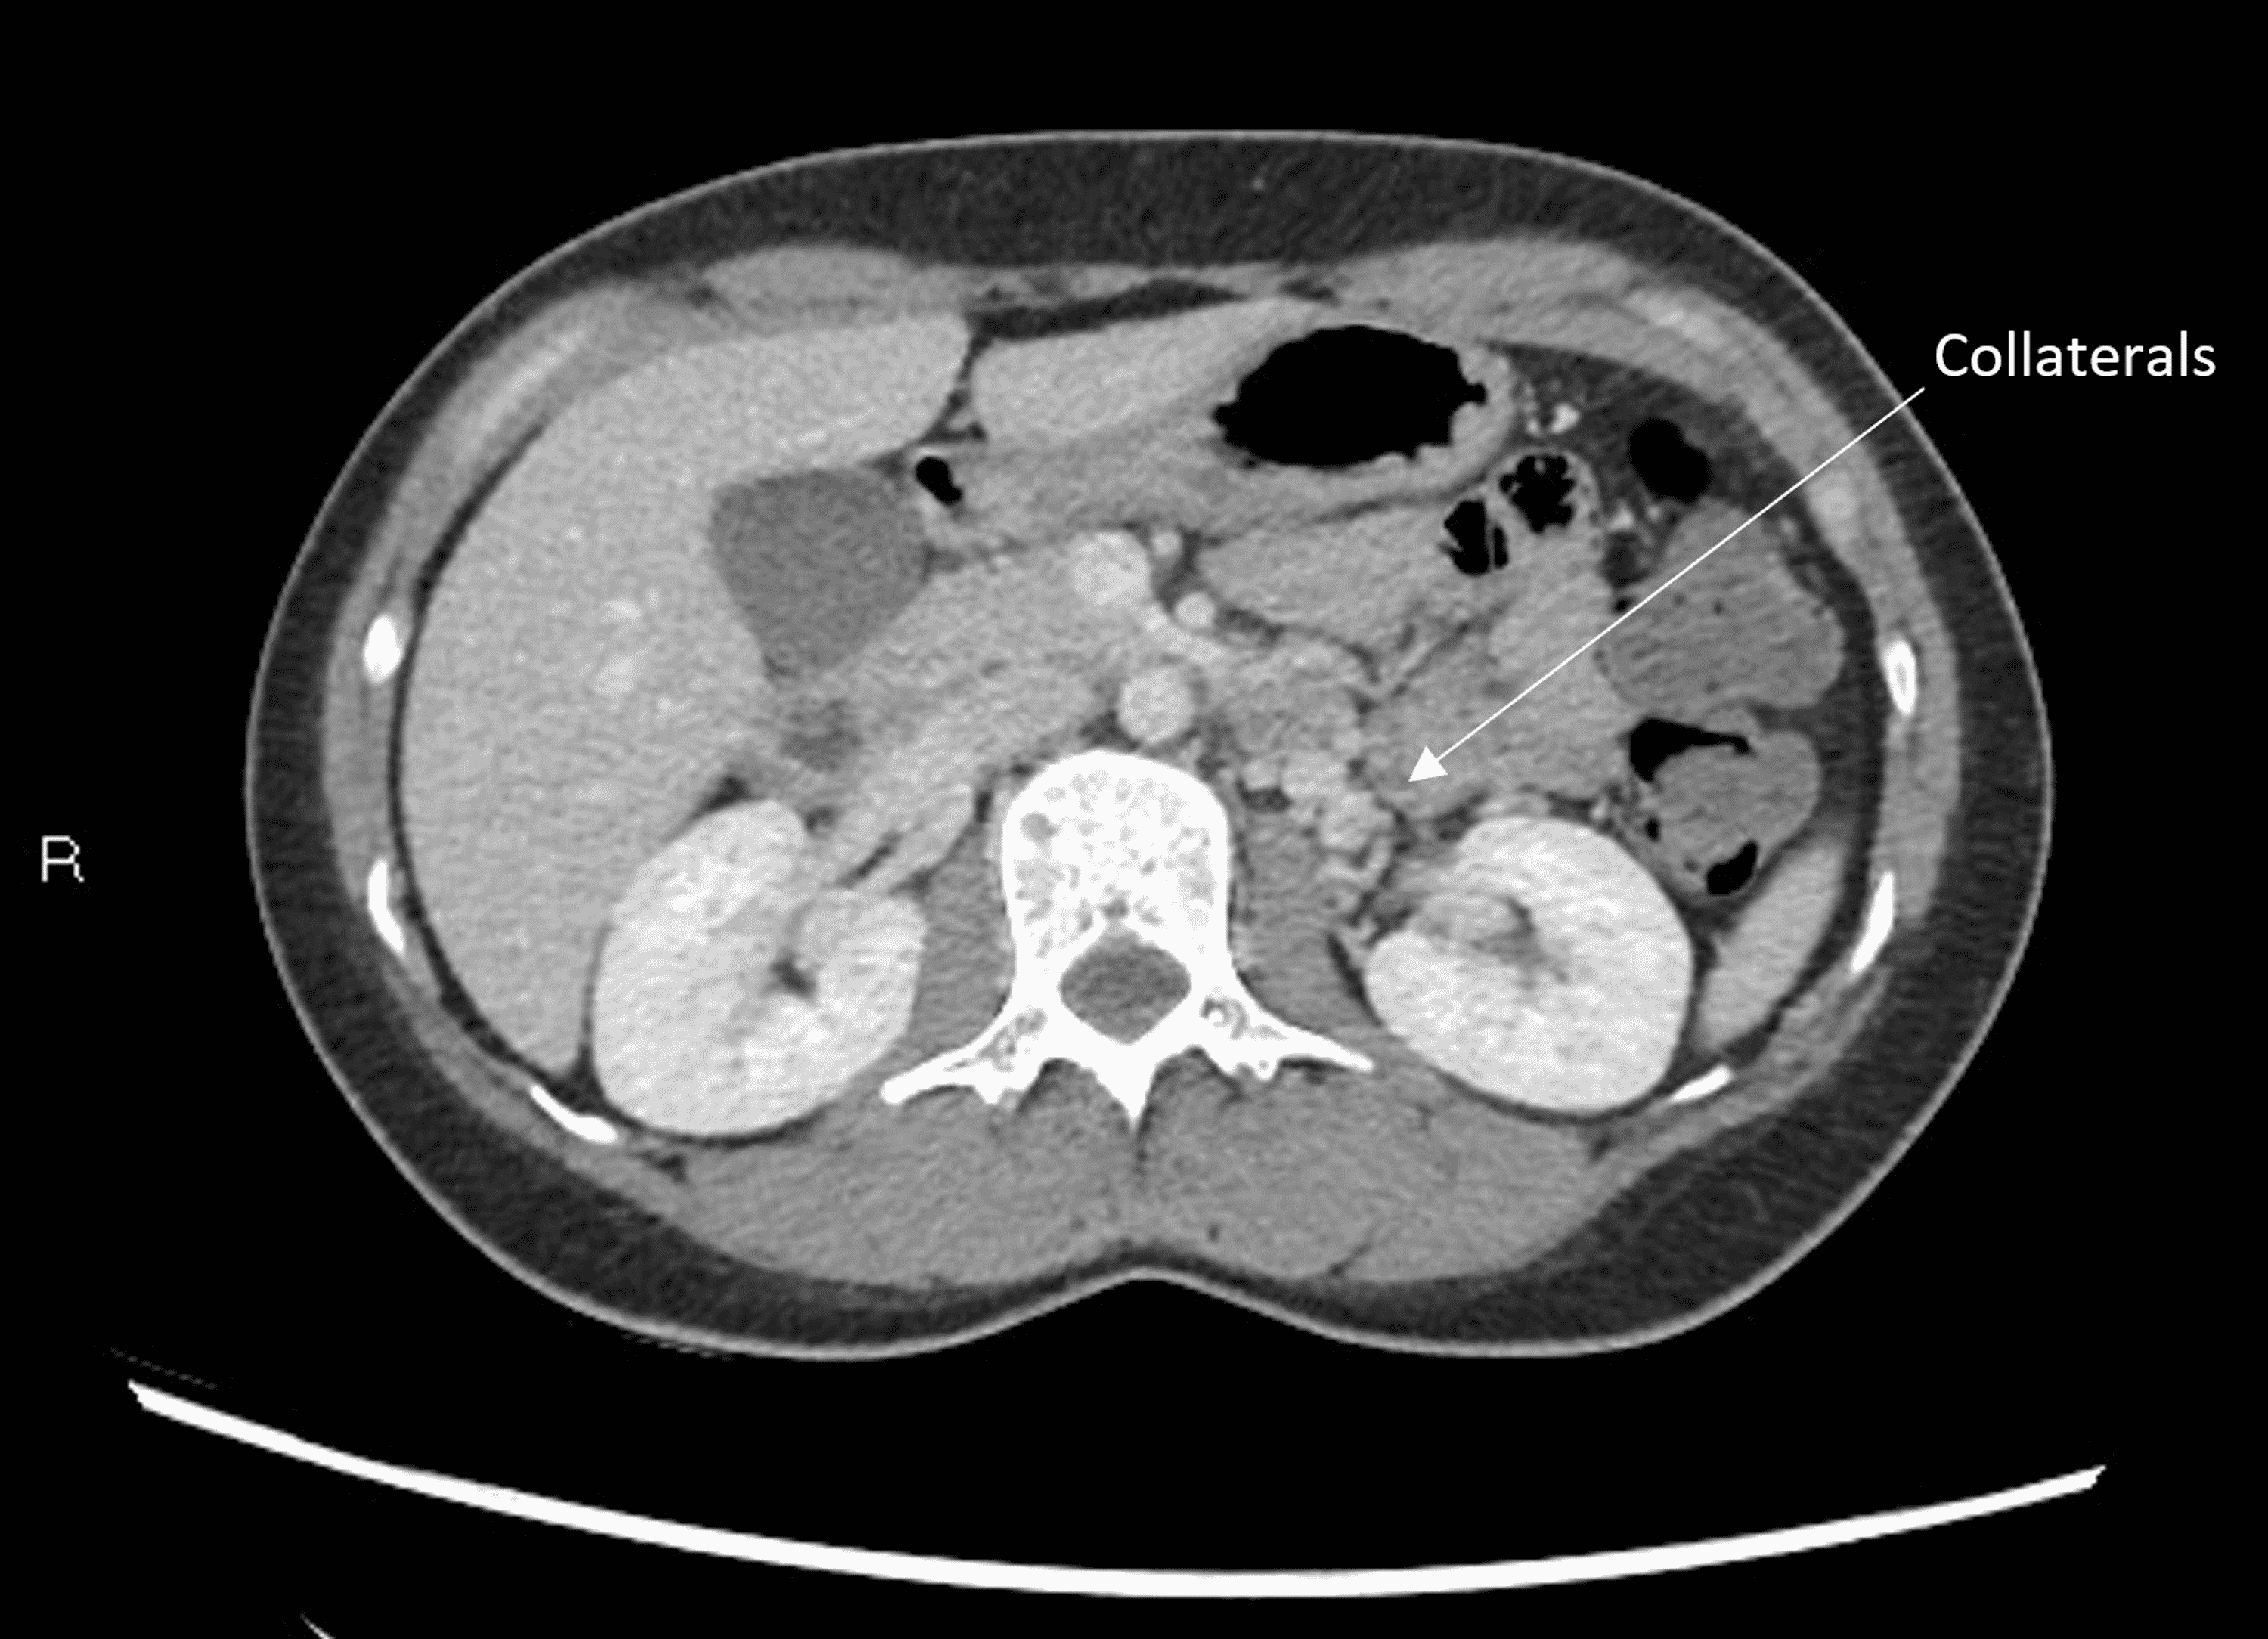

Abdominal MRA images of a patient with nutcracker syndrome. a) axial

Abdominal MRA images of a patient with nutcracker syndrome. a) axial Nutcracker Syndrome Abdominal Pain Entrapment of the left renal vein between superior mesenteric artery and aorta is known as nutcracker phenomena, while. Nutcracker syndrome (ncs), a rare but impactful vascular condition, emerges from the compression of the left renal vein by adjacent. Nutcracker syndrome (ncs) is an extrinsic compression of the left renal vein (lrv) by the superior mesenteric artery (sma). The most common. Nutcracker Syndrome Abdominal Pain.